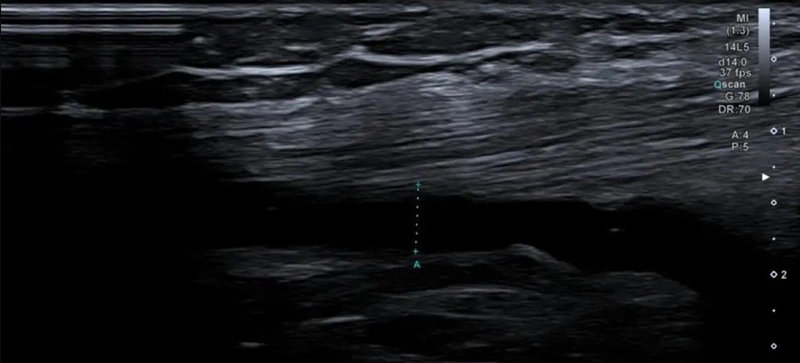

Для проведення УЗД колінного суглоба потрібно звільнити досліджувану область від одягу. Шкіра змащується контактним гелем, датчик прикладається до поверхні коліна і пересувається таким чином, щоб забезпечити якомога кращу візуалізацію структур — сухожиль, зв'язок, меніска, синовіальної сумки. Лікар визначає, чи наявні ушкодження, ознаки запалення, дегенеративних змін, рубці, пухлини та інші патології, фіксуючи результати у протоколі дослідження. Процедура проходить без болю та дискомфорту.